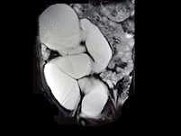

- 多项选择题女,28岁, 持续性腰痛加重2天,伴尿频、尿急、尿痛及发热, MRI如图所示,下列说法正确的是 ( )

A、单侧输尿管明显扩张,同侧的肾盂肾盏也扩张,但其程度轻于前者

B、考虑为先天性巨输尿管

C、考虑为输尿管下端结石并积水

D、考虑为输尿管癌所致的梗阻积水

E、考虑为输尿管囊肿